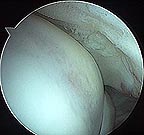

Arthroscopy Pictures of a Partial Rotator Cuff Tear

Partial rotator cuff tear